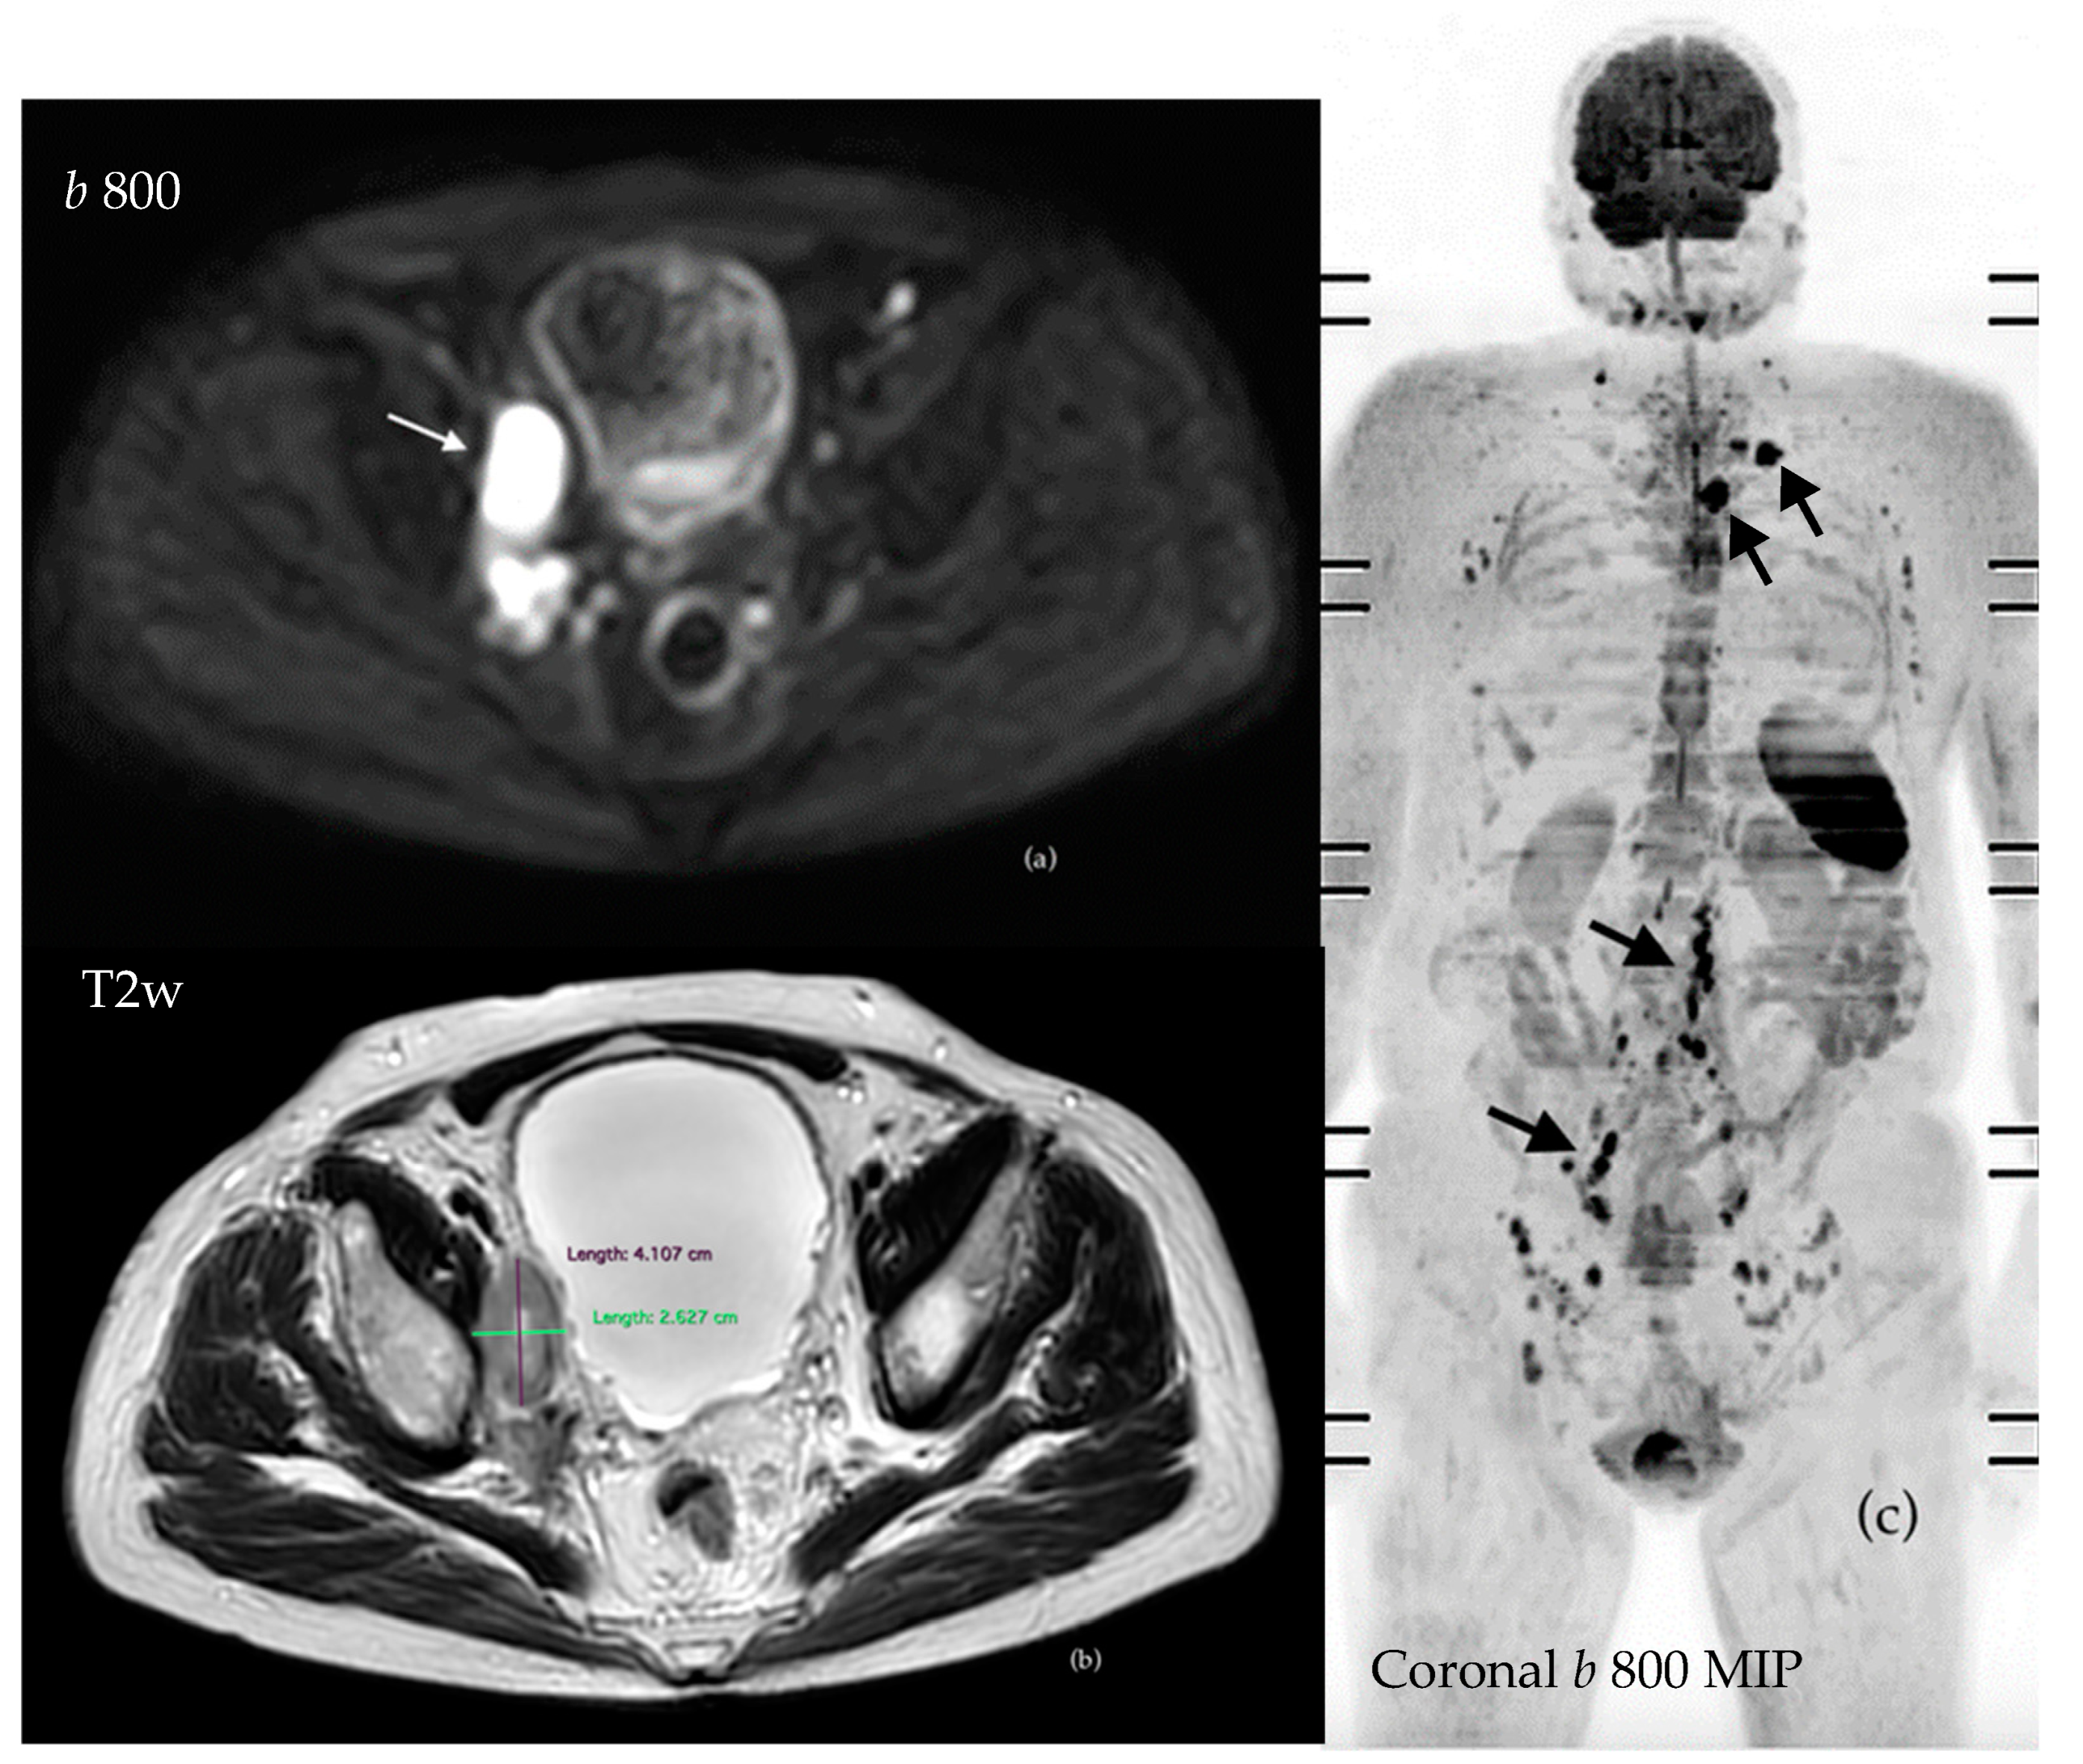

3.4. Imaging Features of Metastatic PC in WB-MRI

3.4.1. Evaluation of Bone Metastases with WB-MRI

3.4.2. Assessment of Nodal Disease